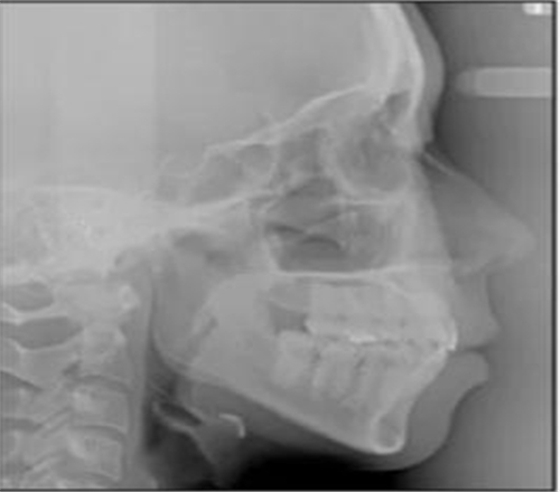

治療后數(shù)據(jù)提示治療目標(biāo)達(dá)成。面相結(jié)果提示微笑及側(cè)貌得到改善(圖6)。達(dá)到了安氏I類尖牙關(guān)系和安氏II類磨牙關(guān)系,形成尖牙保護(hù)合。牙齒中線無偏斜,達(dá)到理想的覆合覆蓋,Spee曲線得到整平。

治療后全景片提示間隙得到關(guān)閉,除了左下頜第一前磨牙外牙根平行度可,無明顯骨及牙根吸收。(圖7)

治療后頭側(cè)數(shù)據(jù)提示:無明顯骨性變化(上頜SNA82.1°,下頜SNB74.9°),上頜前牙得到內(nèi)收,略舌傾,頦部前后位置無明顯改變,仍未凸面型(圖8,表)。將治療前后圖像重疊后結(jié)果如(圖8及圖9),24月后隨訪結(jié)果見圖10.